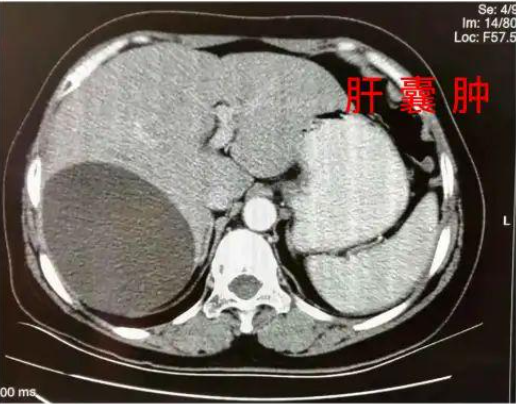

在她看来,不论是医学,还是营养学,其实归根到底,都是调理肝脏等器官功能的手段,最终目的都是让人重启自愈力获得自愈。吃药只是控制指标,控制症状不再恶化,只有饮食补充的营养素,才是给人体补充自愈能量的关键。饭吃的对,就能又瘦又健康。吃不对,身体就会饱受肥胖慢病折磨。李泓霖老师是就是营养食疗法的践行者,这让她如今年过五十看起来仍像三十岁,年年体检都正常。谁能想到,她从小就是个“药匣子”,因为早产,天生体质虚弱,再加上营养不良,身体极差,感冒、发烧、肺炎,是家常便饭,呆在病房的时间比在教室都要长。那时候流行输液,她胳膊上,脚上都扎满了针孔,后来没地方扎针,就从头皮输液!各种抗生素和白药片几乎成了下饭菜,父母担心她的身体,经常夜里叹气、流眼泪。走向社会后,通过打拼,条件好了,但是由于身体基础差,又患上了肝囊肿,卵巢囊肿等疾病。工作时候,由于过于拼命,多次晕倒被120抢救!为了能正常上班,李泓霖只能不断吃药,这也导致肝损伤加重。被折磨的太久了,甚至想过放弃治疗。一次偶然的机会,她接触到了世界自然医学会联合总会主席马永华教授的讲座,了解了营养食疗,让她意识到,只要注意调养,调理好肝损伤,就能重塑代谢系统,80%的疾病都能够自愈。从此,李泓霖老师就踏上了打磨饮食调理法的道路,而她就是第一位试验者和受益者。当她为自己调理了半年后,去体检,医生告诉她可以把药都停了。当时医生都不相信坚持结果,把护士喊来反复确认了好几次!从此,李泓霖老师决定把这套方法造福更多人,她还考取了国家一级营养师和国际注册营养师,成为国家第一批营养师。由于李老师凭借专业的营养学功底知识,用自愈力饮食法帮很多病人调理好了身体,李老师的名声也越传越开。后来她主持开办了北大营养班,邀请国内外营养学专家前来讲学,随后开始全国巡讲。李老师说她在全国巡讲的时候,经常会被问到关于如何瘦身减肥,如何降高压,降血糖,降血脂的问题。其实,这些问题,都可以通过饮食调理,科学饮食改善肝损伤,唤起的自愈力,可以调百病↓李泓霖老师对比了东西方近百种饮食方法,发现国外虽然也有不少好的饮食法,但是和国人的体质和生活环境不是很匹配,为了打磨更适合国人的营养食疗体系,李老师把营养科学和中医结合了起来,并根据国人的身体情况和饮食、养生习惯,联合长轻,研发出了一套4816营养食疗法。这方法是否有效呢?来找李泓霖咨询的人一天比一天人多,火爆的时候,一场直播有数万人同时在线,反馈好评满满,就是最好的证明。@福泽装饰:肝脏脂肪超标检查已经逆转,肝功能也正常了;